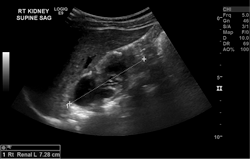

Point-of-Care Ultrasound (POCUS)

Point-of-care ultrasound (POCUS) is a focused ultrasound exam clinician performs at the bedside. POCUS exams improve the accuracy, quality, and efficiency of clinical care.

Examples